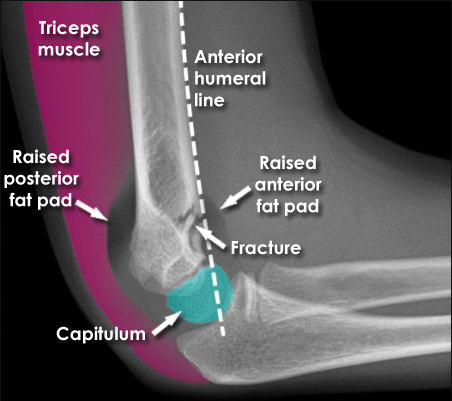

What might you see on x-ray of supracondylar fracture?

What might you see on x-ray of someone with a radial head fracture?

Sail sign (elevation of anterior fat pad)